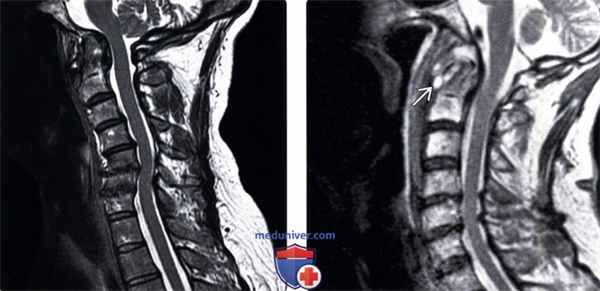

(Слева) Т2-ВИ: пример состояния, требующего дифференциального диагноза с пирофосфатной артропатией. В данном случае это ревматоидный артрит, сопровождающийся «проседанием» черепа на фоне проксимальной транслокации зубовидного отростка в большое затылочное отверстие вследствие несостоятельности связочного аппарата.

(Справа) Т2-ВИ: случай спондилита С1-С2, также включенного в дифференциально-диагностический ряд. Определяются признаки флегмоны С1-С2 сочленения, характеризующейся гиперинтенсивностью сигнала, что кардинально отличает ее от пирофосфатной артропатии, изменения при которой характеризуются низкой интенсивностью сигнала.